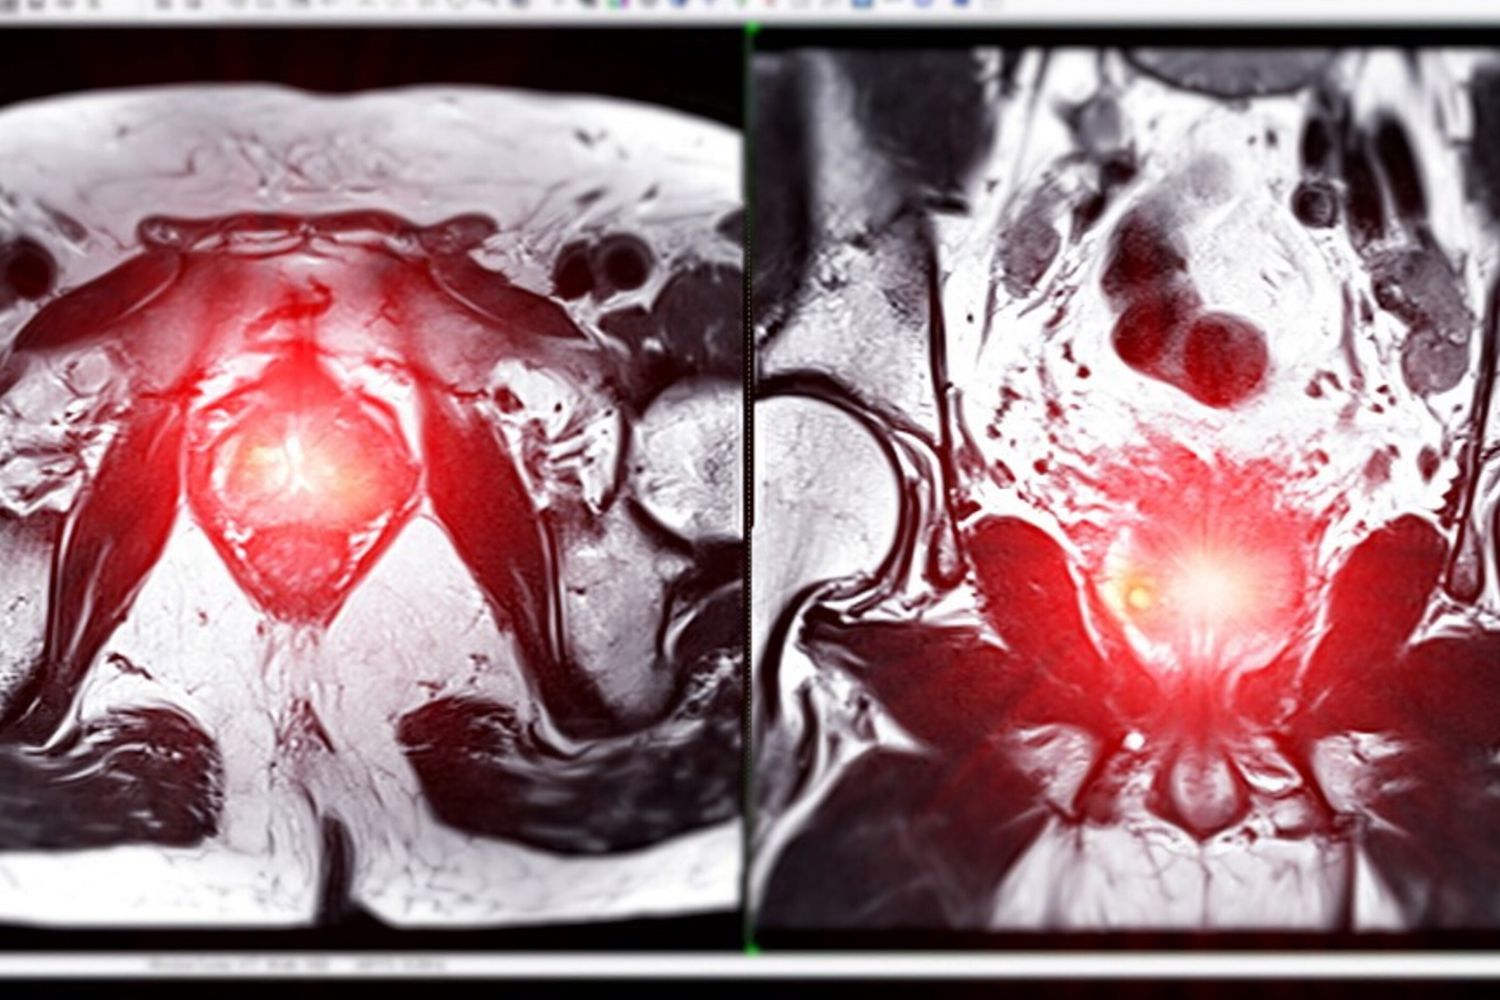

AGI - Una forma tumorale molto seria, vicina al grado massimo di aggressività, capace di diffondersi alle ossa e ad altri organi. Questa la situazione clinica dell'ex presidente Usa Joe Biden, che soffre, è stato annunciato, di un cancro alla prostata caratterizzato da un punteggio di Gleason di 9, con metastasi ossee.

Quando la massa tumorale cresce, dà origine a sintomi urinari: difficoltà a urinare (in particolare a iniziare) o bisogno di urinare spesso, dolore quando si urina, sangue nelle urine o nello sperma, sensazione di non riuscire a urinare in modo completo. I tumori con grado Gleason 8-10, come quello di Biden, per definizione hanno un maggior rischio di progredire e diffondersi in altri organi.